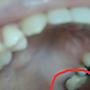

後面的上排臼齒蛀空 已經做了根管治療 目前正在尋找台北技術好又較便宜的牙醫做牙套 今天有打電話過去問 護士小姐說 合金的8000 白金 12000 黃金90% 20000 全瓷冠 20000 問了我爸 他說白金就很耐用 而且臼齒也看不太到 目前再考慮白金跟黃金 是否真的會差很多呢?? 謝謝^^ -- ※ 發信站: 批踢踢實業坊(ptt.cc) ◆ From: 123.192.82.128